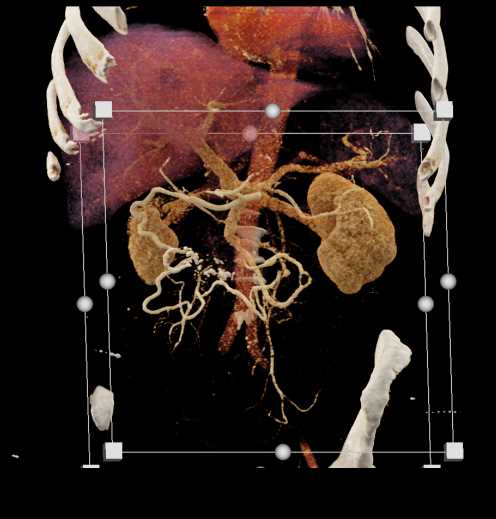

Carcinoid Tumor with Desmoplastic Reaction